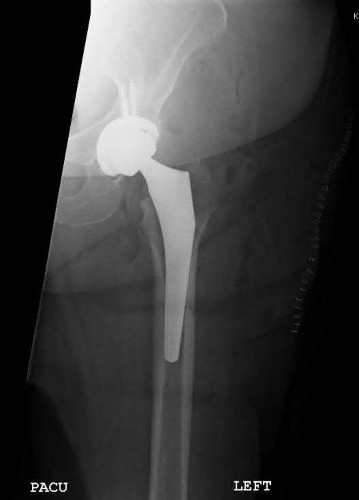

A 76-year-old male community ambulatory presented to clinic complaining of pain in the left groin that has been persistent for the last 8 months. Radiographs obtained from clinic are seen in Figure A. You suspect a femoral neck nonunion and obtain a CT scan which confirmed it. Which of the following statements is true?

A total hip arthroplasty (THA) after nonunion of a femoral neck fracture would provide the best long term outcomes in a 76-year-old male who is a community ambulator.

After nonunion of a femoral neck fracture, hemiarthroplasty and THA are good salvage option for the physiologically older patients. When deciding between these two options, THA is better for active and cognitively intact patients. THA is also indicated in patients with radiographic evidence of degenerative disease about the acetabulum. Hemiarthroplasty is advocated for patients who are older and less active.

Yang et al. retrospectively investigated the risk factors for nonunion in patients treated with cannulated screws. They reviewed 202 patients who had femoral neck fractures and were treated with internal fixation with cannulated screws. They identified that triangle configuration, displaced fracture, borderline or unacceptable reduction, and increased screw shaft subchondral purchase over the femoral neck were all risk factors for nonunion after internal fixation.

Inverted triangle configuration was found to increase rate of union.

Archibeck et al. retrospectively reviewed the outcomes of 102 THAs after failed internal fixation for a hip fracture (including both femoral neck and intertrochanteric). They concluded that the conversion of failed hip internal fixation has elevated risks compared to a primary THA, however, it may still be successful. The biggest concern for these patients postoperatively are periprosthetic fracture and dislocation.

Figures and Illustrations:

Figure A is an AP pelvic radiograph demonstrating a nonunion of a femoral neck fracture after suboptimal fixation with 3 cannulated screws in a triangle configuration.

Illustration A is an AP radiograph of the left hip in this patient following conversion to THA.

Illustration B is a radiograph demonstrating a valgus osteotomy. Illustration C shows an example of a femoral neck nonunion with varus malreduction.

Incorrect Answers:

Answer 2: Varus reduction is closely correlated with failure in this fixation method.

Answer 3: The patient's best outcome would be with THA.

Answer 4: This would be a good option in a younger patient, but given age and functional capacity, the best option is THA.

Answer 5: Patients with hemiarthroplasty have lower rates of dislocation.